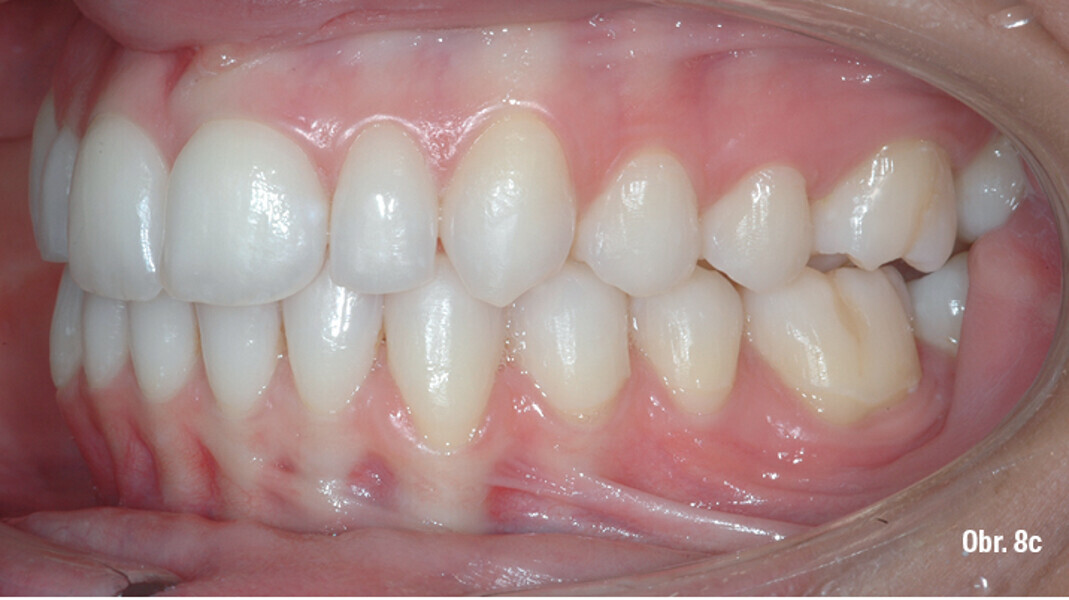

Distalizace horních molárů pomocí alignerů a cyklických sil